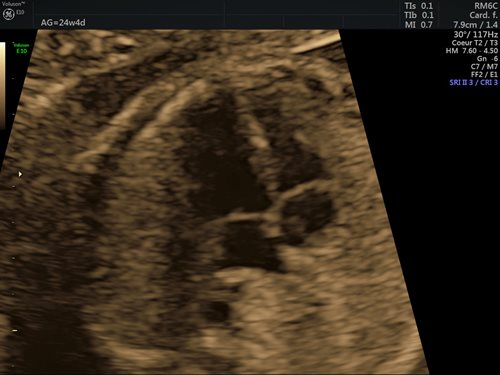

Dans la grande majorité des cas (90 %), l’étiologie des cardiopathies congénitales est multifactorielle, un facteur de risque classique comme des antécédents familiaux au 1er et 2e degré, la présence d’une anomalie chromosomique, d’un diabète maternel de type 1, d’une phénylcétonurie, la prise de certains médicaments ou une infection n’étant pas retrouvé. Pour cette raison, un dépistage systématique par échocardiographie foetale reste indispensable, idéalement entre 18 et 22 semaines de gestation. Le dépistage recommandé consiste en l’obtention d’une vue des 4 cavités cardiaques (fig. 1) et d’une vue des voies d’éjection (fig. 2). (2)

Figures 1